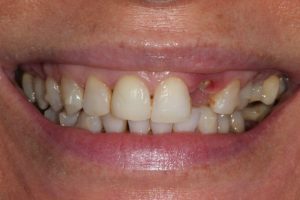

Full Mouth Rehabilitation

Full mouth Treatment – missing upper front teeth and mispositioned implants in the Lower left side meant planning was key here to get the desired result. Implants were placed to replace the missing teeth, veneers/crowns on the remaining upper teeth allowing an improvement in overall shape and colour, and the implant crowns on the lower left were change to bring into the line of the bite.